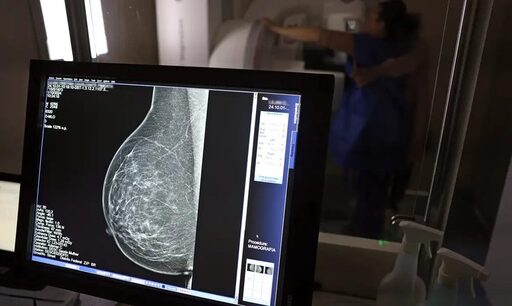

• JOSÉ CRUZ/AGÊNCIA BRASIL -

Programa Agora Tem Especialistas amplia prevenção e tratamento oncológico no SUS: 781 mil casos projetados pelo INCA até 2028, mamografias para 40-74 anos, recorde em quimioterapia e vacina HPV a 85%. Avanços reais para diagnóstico precoce e equidade. Fonte: Ministério da Saúde e INCA.

Mamografia gratuita para mais mulheres

Agora, mulheres de 40 a 49 anos – mesmo sem sintomas – podem fazer mamografia no SUS, além de 50 a 74 anos. Em 2025, foram 3 milhões de exames bilaterais, e a Pesquisa Vigitel/MS 2025 mostra que 92% das mulheres de 50-69 anos já realizaram o teste. Isso eleva as chances de cura em até 90% nos estágios iniciais.